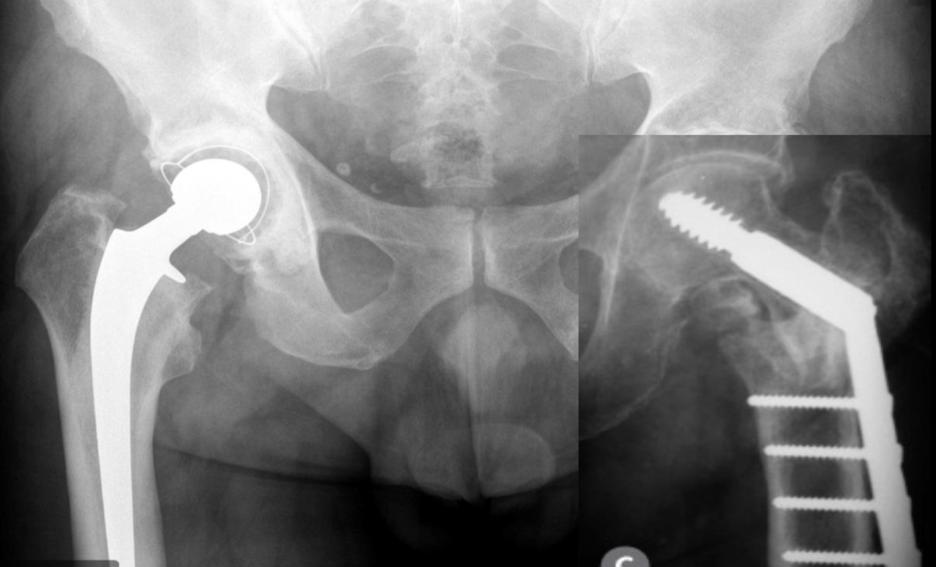

Aparte, os aclaro como son las fracturas de cadera o fémur y las técnicas de unión de dicha fractura.

Esto es efectos solamente de conocimiento, por si alguien nos viene con prótesis de cadera

Bueno, y de esto me faltaba aclarar que no es lo mismo fractura de pelvis que fractura de cadera.

La pelvis son todos esos huesos, excepto el fémur que inserta en la pelvis.

Las fracturas de pelvis suelen ser por accidentes severos o caídas de personas muy mayores con avanzada osteoporosis

Fractura subcapital es lo mismo que fractura de cuello de fémur